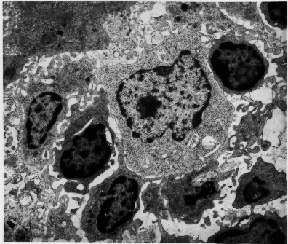

Figure 12. Very few cancer cells survive in the bloodstream. Mechanical stress shears the cancer cells, and immune cells attack them. When they recognize the cancer cells as foreign, white blood cells surround cancer cells as shown in this photomicrograph. White blood cells sometimes kill the cancer cells. Recent studies have shown, however, that some cancer cells have developed the ability to evade the immune system or to kill the attacking white blood cells. (Photomicrograph courtesy of Patrizia Griffini, Academic Medical Center, University of Amsterdam.)